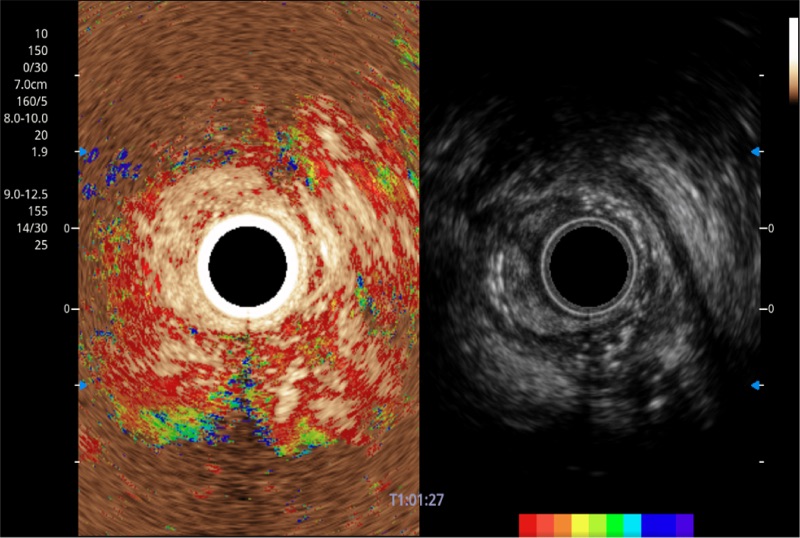

• 伪彩(Chroma)

可人为将灰阶图像转变成彩色的显示方式,增强人眼对于不同回声强度的敏感度,主观上增加了图像分辨率

• 非线性融合造影

融合谐波技术

动态声压控制技术

TIC时间强度分析曲线

具有四种造影成像效果